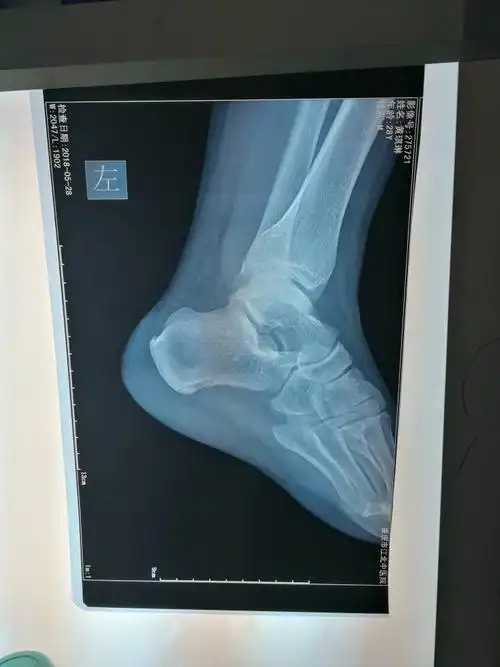

阿姨每天跳3小时广场舞脚底长"钉子",反复足跟刺激是产生骨刺主因

脚跟骨刺祖传秘方

脚后跟红肿疼痛是骨刺吗

脚和脚后跟疼痛, 足底筋膜炎, 特写脚跟骨刺诊断

关节镜下切除跟骨骨刺治疗顽固性足跟痛_骨质增生_介绍_治疗方式 - 好

脚后跟长骨刺